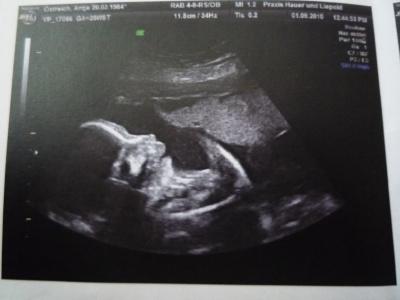

Huhu ich bin wieder da. Also die Maus ist Mopsfidel. Es war schön sie kurz zu sehen. Die kleine ist knapp 35cm gross und hat 700g, laut FA völlig im Rahmen. Der Doppler war auch perfekt, der hätte wohl nicht besser laufen können. Da die SS momentan so gut verläuft, traute ich mich doch glatt mal zu fragen ob ich evtl. doch aussicht auf eine Spontane Geburt hab. Dies verneinte er allerdings. Er meinte das ich sicher keinen Finde der dieses Risiko auf sich nimmt. Na toll...ich habe doch soo gehofft. Nun ja dann werde ich mal in dem KH hier in der Nähe mal einen KS Termin ausmachen. Ich habe ihm gefragt was bei ihm der 3D kostet...ganze 111€ ich habe ihm dann erzählt das es hier extra ein Studio dafür gibt wo es nur 80€ kostet und die darauf spezialisiert sind. Er meinte beim 3. Screening in 4 Wochen werden wir mal verhandeln. Ich hoffe ja das er sich im Preis etwas drücken lässt. *hoff* Um zu zeigen das er ein gutes US Gerät hat, hat er doch glatt mal schnell auf 3D umgestellt. Komisch wie real das ganze auf einmal wird wenn man die Mäuse soo genau erkennt. Die Zeit rennt einfach. Wenn ich bedenke das ich dann so langsam den Termin für den KS ausmache. So in 4 Wochen, also am 29. darf ich die Maus dann wieder sehen. Ich hoffe die Zeit vergeht schnell. LG Antje

Bild zu Zurück von der VU mit Bildchen - Forum für Dezember - Mamis